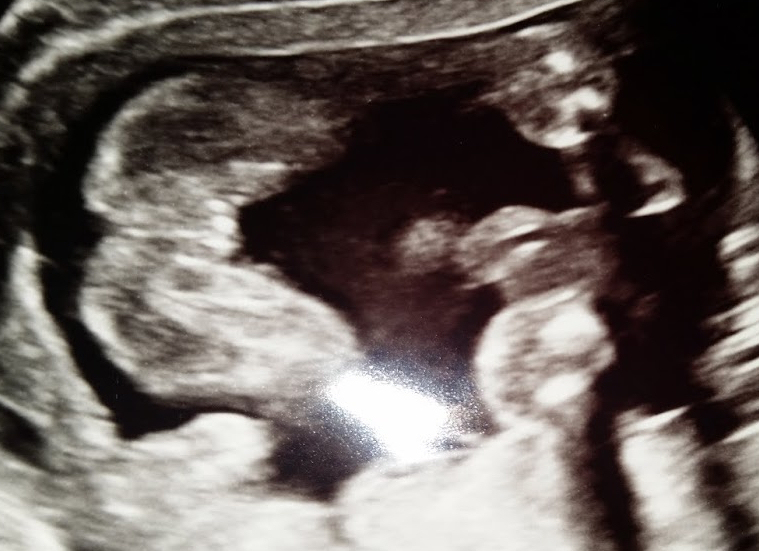

3rd baby and hubby and I decided not to have the tech confirm gender, just to give us pics to look at privately together (Since we have a boy and girl we should be able to figure it out right?) Apparently not, we disagree as to what we are seeing!

Attachment 25467

Attachment 25468